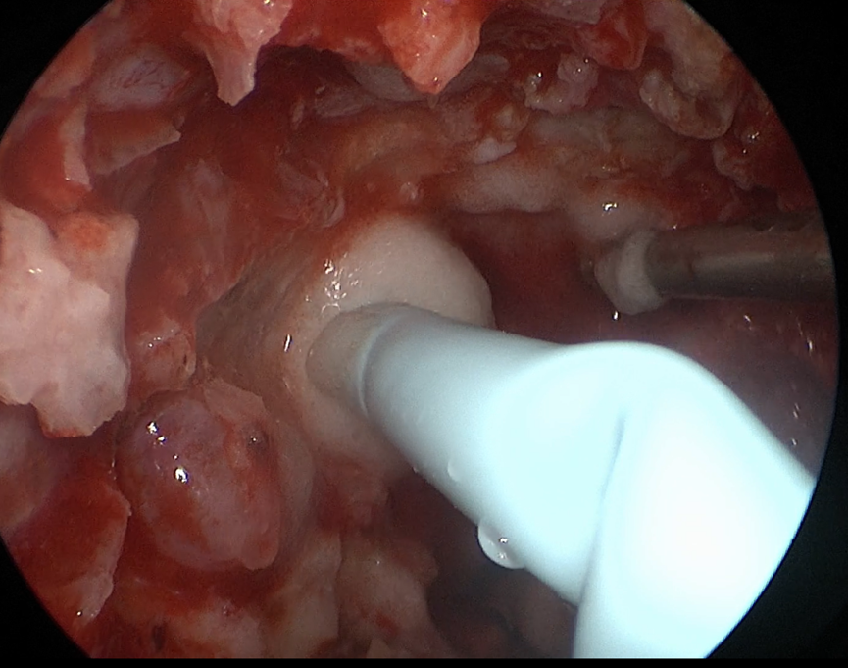

自近蝶窦前壁处向左侧推挤鼻中隔,离断筛骨垂直板,咬除部分近蝶窦处骨性鼻中隔,分离双侧鼻粘膜显露蝶窦前壁,自蝶窦开口上方做沿鼻中隔做粘膜瓣备用,末端到中鼻甲位置,将粘膜瓣压向下鼻道,高速磨钻磨除蝶窦下壁骨质,鞍结节骨质。术中视神经管清晰可见,给予保护,海绵间窦出血给予流体明胶+凝血酶止血;等离子刀一边止血一边切开硬脑膜见白色肿瘤质韧,边界清晰,大脑前动脉分支粘连于肿瘤表面,给予小心分离,以刮圈,咬切钳等小心清除肿瘤组织;内镜下将肿瘤完整切除;取右侧大腿皮下脂肪及阔筋膜备用,以人工硬膜修补和明胶海绵封闭鞍底硬膜,将脂肪放置于切口,并缝合于鞍底硬脑膜上固定铺平,阔筋膜覆盖于脂肪外边,蝶窦内充填明胶海绵止血,鼻粘膜瓣覆盖于蝶窦;碘仿纱条填塞鼻腔;护士清点棉条、器械、纱布无误,撤出鼻镜。